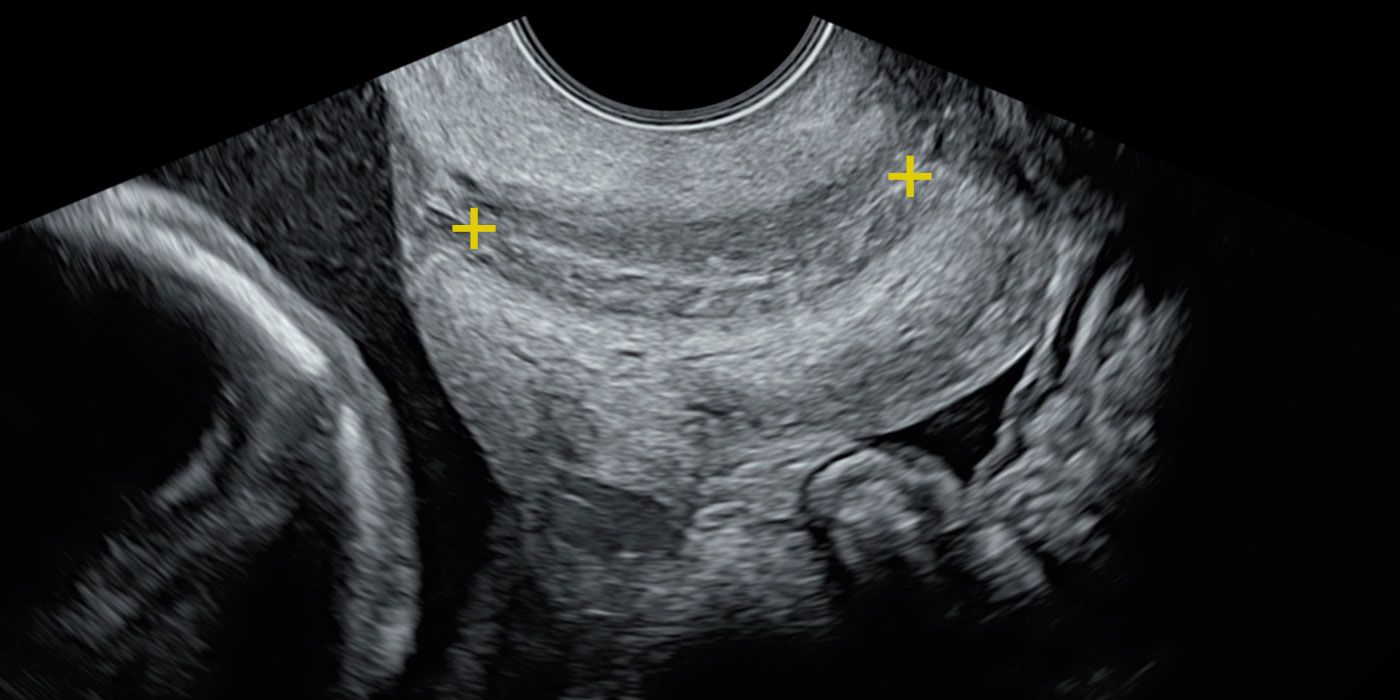

Transvaginal Scan for Measurement of Cervical Length

The only correct way to measure the cervix is by transvaginal scan (TVS). This approach represent unique window to check the structures deeply hiden in your pelvis and poor visible by transabdominal scan. Those structures are lower part of the womb, presenting (lower) parts of the baby and other intrapelvic structures.